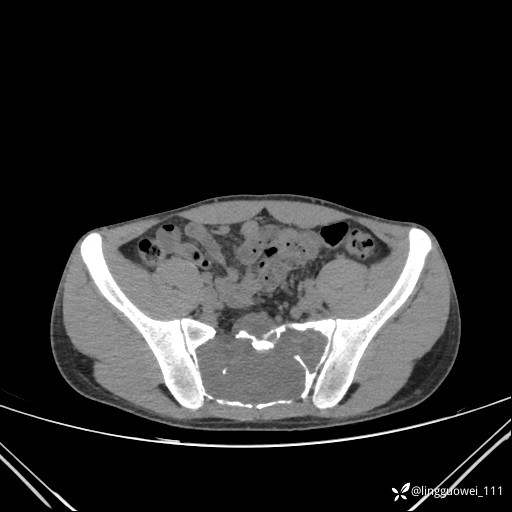

男,25岁,腰痛4年,加重左下肢痛5天,先上传X光片,第2天再上传CT。MR

静脉期:

MR:(忘记截图常规序列,不过应该不影响诊断)